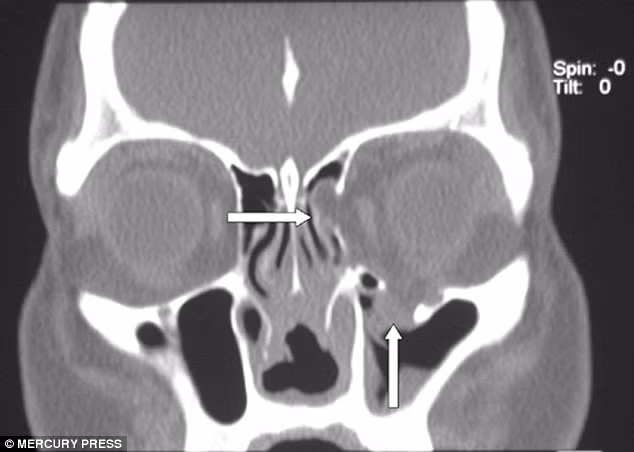

Cho đến khi bác sĩ tiến hành chụp x-quang chiếc mũi cô, họ phát hiện ra cô gái đã bị nhiễm necrotising fasciitis - một loại bọ ăn thịt người có thể ăn mòn các mô mềm của cơ thể. Các bác sĩ cảnh báo rằng nếu loại bọ ăn thịt người này xâm nhập sâu vào bên trong khuôn mặt của cô, chúng có thể giết chết cô.

Năm 2008, Lois phải trải qua ca phẫu thuật cắt bỏ vùng nhiễm khuẩn và những phần thịt hoại tử bên trong khuôn mặt.